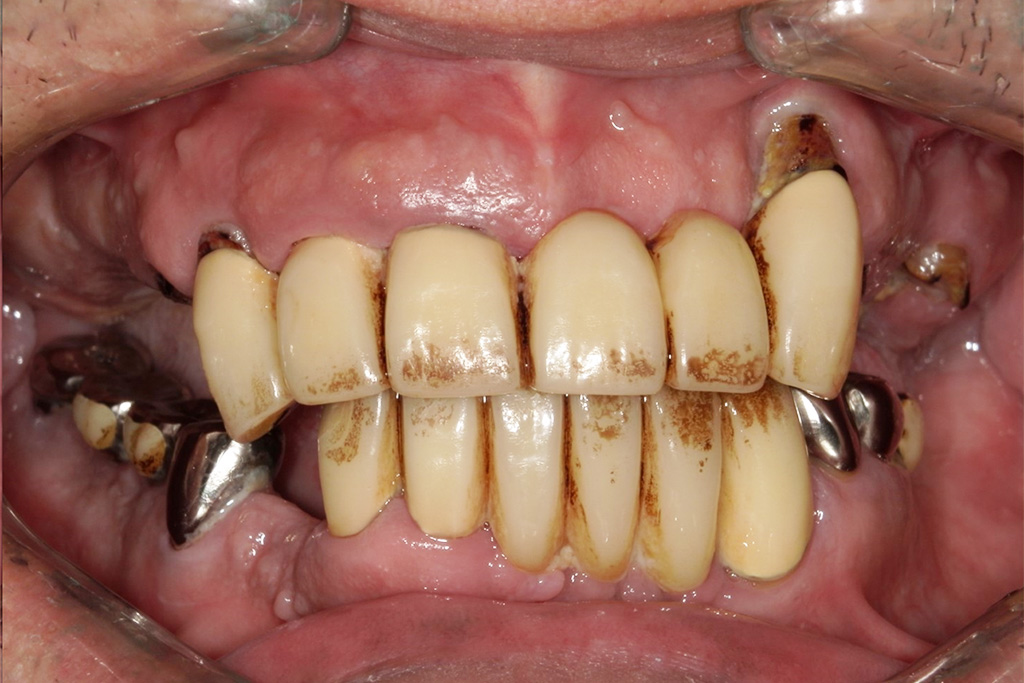

Hさまは今まで歯医者が嫌いで行かないでそのまま放置していました。タバコもヘビースモーカーと自分で言うくらいの量を吸っていたそうです。

放置していたらどんどん歯がボロボロになっていき、噛めないことと痛みがあるのでどうしたらいいかと、重い腰を上げてきてくださいました。

奥さんにインプラントがいいと言われたからインプラントを知りたいとのことでHPを見てきてくれたそうです。

今回は噛めることと見た目の改善を目的として上顎はダメな部分は抜歯をし、インプラントを入れました。

Hさまのインプラント治療は1年かかりました。理由としてはヘビースモーカーのためインプラントが骨と定着しなかった部分があったため何本か抜けてしまったりし、再度インプラントを入れ直したり等したためです。

タバコを止めることがストレスになるとのことでした。インプラント治療には禁煙は必須ですがストレスのが強いのであれば、インプラントが定着せず抜けてしまう可能性は増えますが、辛抱強く行えばインプラントはいつかは定着すると私も勉強させられました。

ヘビースモーカーでも治療が可能と今では言える様になりました。(歯科医師としては言ってはいけないと思いますが・・・)

現在では硬いものもかめてやってよかったと言われて私は満足しかありません。

かなりボロボロでもこのような難症例であろうと私は治療ができると自信がつきました。

今では定期検診でしっかりと予防を行っていただいています。

チェックの日に先生と話すの楽しいと言ってくれてとても私は幸せです。